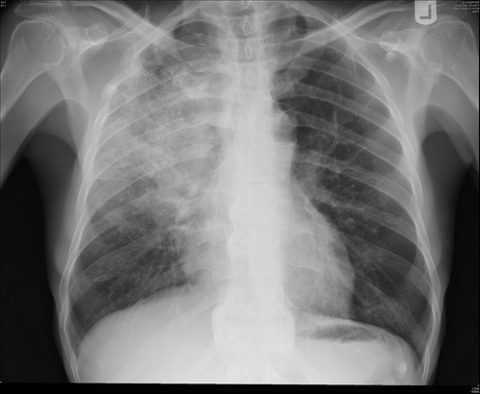

- Гемоторакс. Попадание крови в область плевры диагностируется после рентгеновского обследования. Большое скопление жидкости проявляется в симптомах тахикардии, снижения давления, отсутствия везикулярного дыхания. Явные признаки патологии сигнализируют о необходимости экстренной госпитализации. Откачивание скоплений крови, установка дренажа жизненно важны.

Гемоторакс при переломе ребер

При попадании крови в плевральную полость диагностируется пневмоторакс.

Диагностика и признаки гемоторакса

В большинстве случаев гемоторакс можно обнаружить только при рентгеновском обследовании.

Однако если имеет место большой гемоторакс, он диагностируется и «на глаз». Следует знать, что это не очень хороший факт, требующий скорейшей госпитализации больного.

Признаками большого гемоторакса является наличие:

- тахикардии;

- пониженного давления;

- перемещения сердечного толчка в неповрежденную сторону;

- нет везикулярного дыхания;

- на поврежденной стороне легочной звук притуплен.

Присутствие симптомов большого гемоторакса должно подвигнуть людей, оказывающих первую помощь пострадавшему, на скорейшее перемещение его в больницу, так как нет никаких вариантов спасения человека без скорейшей операции.